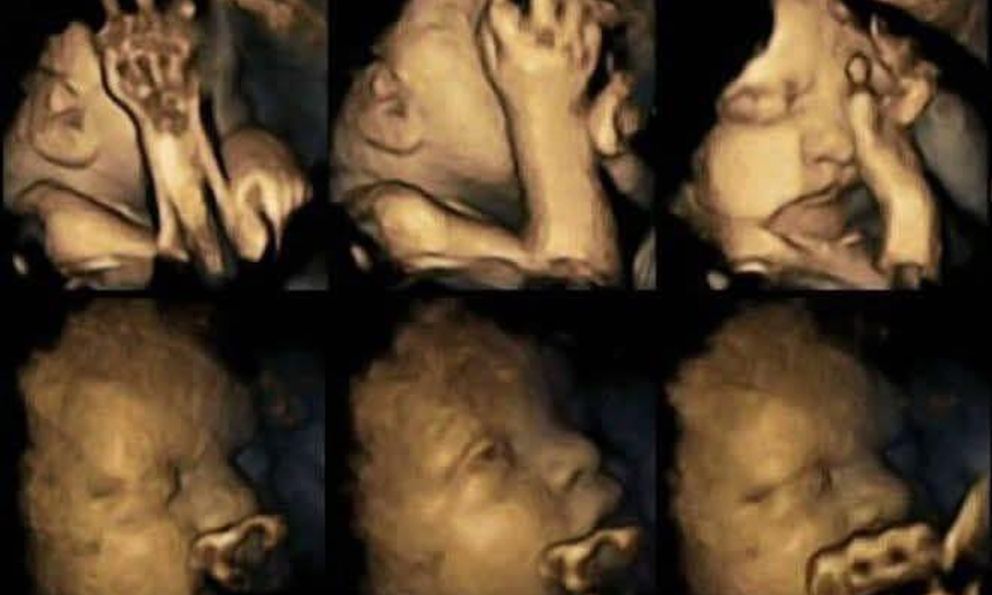

Thai nhi phản ứng với khói thuốc ngay từ trong bụng mẹ

Theo kết quả ghi nhận được của các chuyên gia thuộc Đại học Durham, rõ ràng là thai nhi có những biểu hiện rất khác thường khi bà bầu hút thuốc lá hoặc khi thai phụ tiếp xúc với khói thuốc, cụ thể là em bé thường xuyên đưa tay lên che mặt và khuôn mặt thì rất căng thẳng và nhăn nhó. Kết quả nghiên cứu thông qua việc siêu âm thai cũng cho hay, phụ nữ tiếp xúc với khói thuốc lá trong thai kỳ có thể ảnh hưởng đến hệ thống thần kinh trung ương, và làm trì hoãn sự phát triển của bộ phận này.